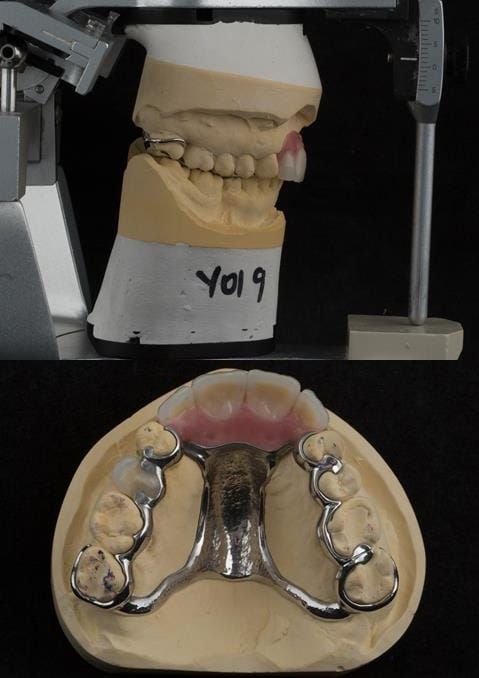

- Extract the upper 2-2 teeth and replace with an interim acrylic based partial denture. Reline the interim denture over 9 - 12 months, replacing with a definitive cobalt chromium based partial denture. The definitive denture would ideally be designed as an occlusal protective splint to reduce the the potential for mechanical wear and breakages of the moderately/heavily restored maxillary dentition. In addition, should further upper teeth require extraction they could be added on to the denture cobalt chromium framework - therefore a new prosthesis would not be required as future teeth are lost. This option would produce an excellent aesthetic outcome. This is the option the patient chose to have.

Following consultation and second discussion appointment the patient chose to have option 3 namely, a maxillary cobalt chromium based partial denture/protective occlusal splint. The clinical situation and treatment process is shown in detail below with photographs. The patient was successfully rehabilitated with this and her quality of life considerably improved. The clinical work was provided by Finlay and the technical work by Rowan.